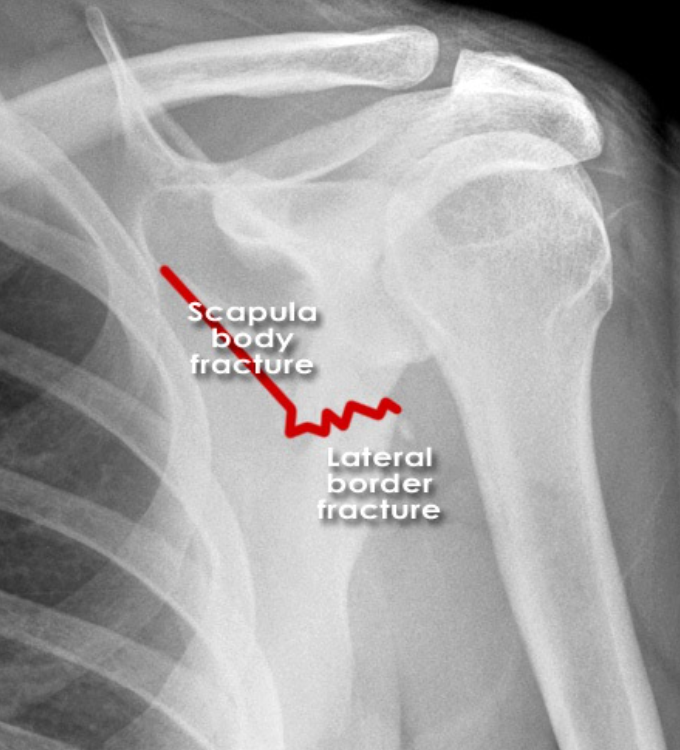

Describe the classification of scapular fractures (4)

Which is most common?

A

Type I-

- acromion process

-scapular spine

-coracoid process

Type II

scapular neck

Type III

intra-articular # of glenoid fossa

Type IV

scapular body

***most common